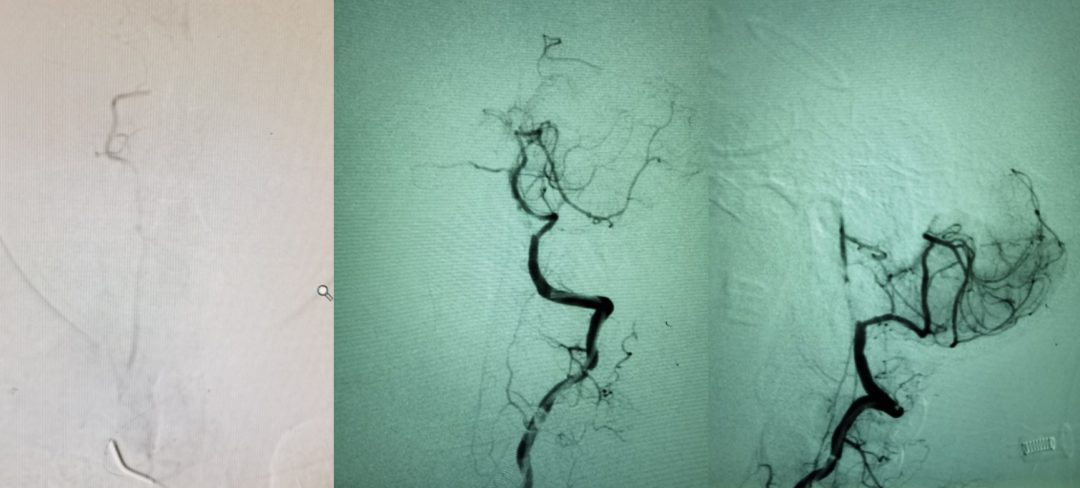

5F 115cm远端通路导管超选至左侧椎动脉V3段,选取术中工作角度造影。

Echelon-10微导管、200cm FATHOM微导丝配合技术通过闭塞节段,微导管内路途提示进入右侧大脑后动脉。

留置300cm FATHOM微导丝,撤出微导管后造影,似乎有了一点正向血流,但压力不够,被逆向血流冲淡。

引入加奇SacSpeed® 2.0mm×12mm颅内球囊扩张。

扩张后造影,提示恢复正向血流,残余狭窄50%左右。

换用加奇SacSpeed® 2.5mm×12mm颅内球囊扩张。